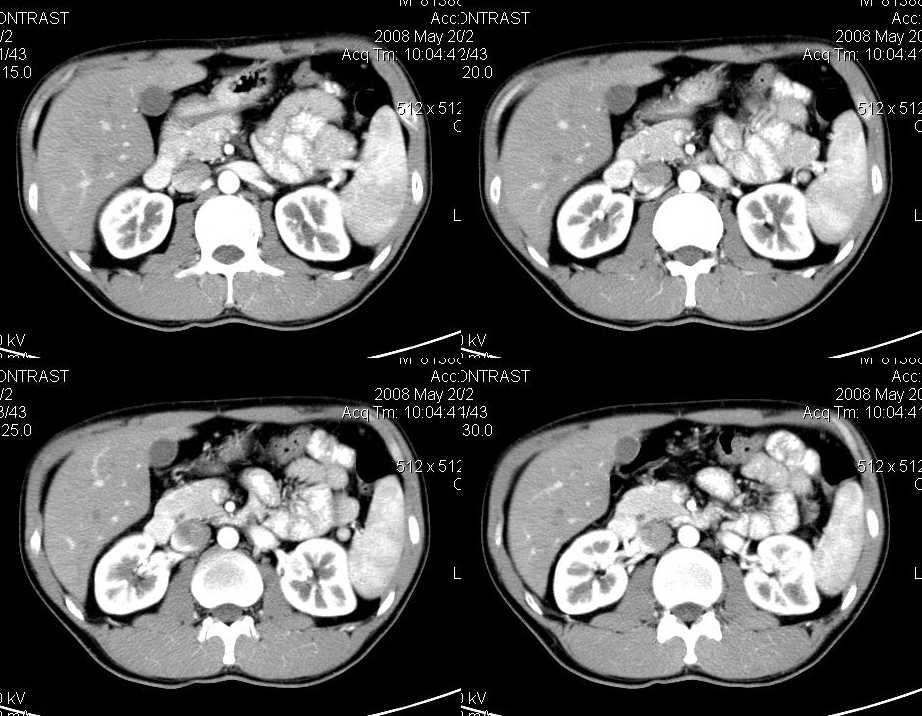

以下是引用liuyue在2008-6-7 15:28:00的发言:[br]典型的:肾癌。[br]动脉期强化明显,而静脉期密度明显降低,呈低密度。